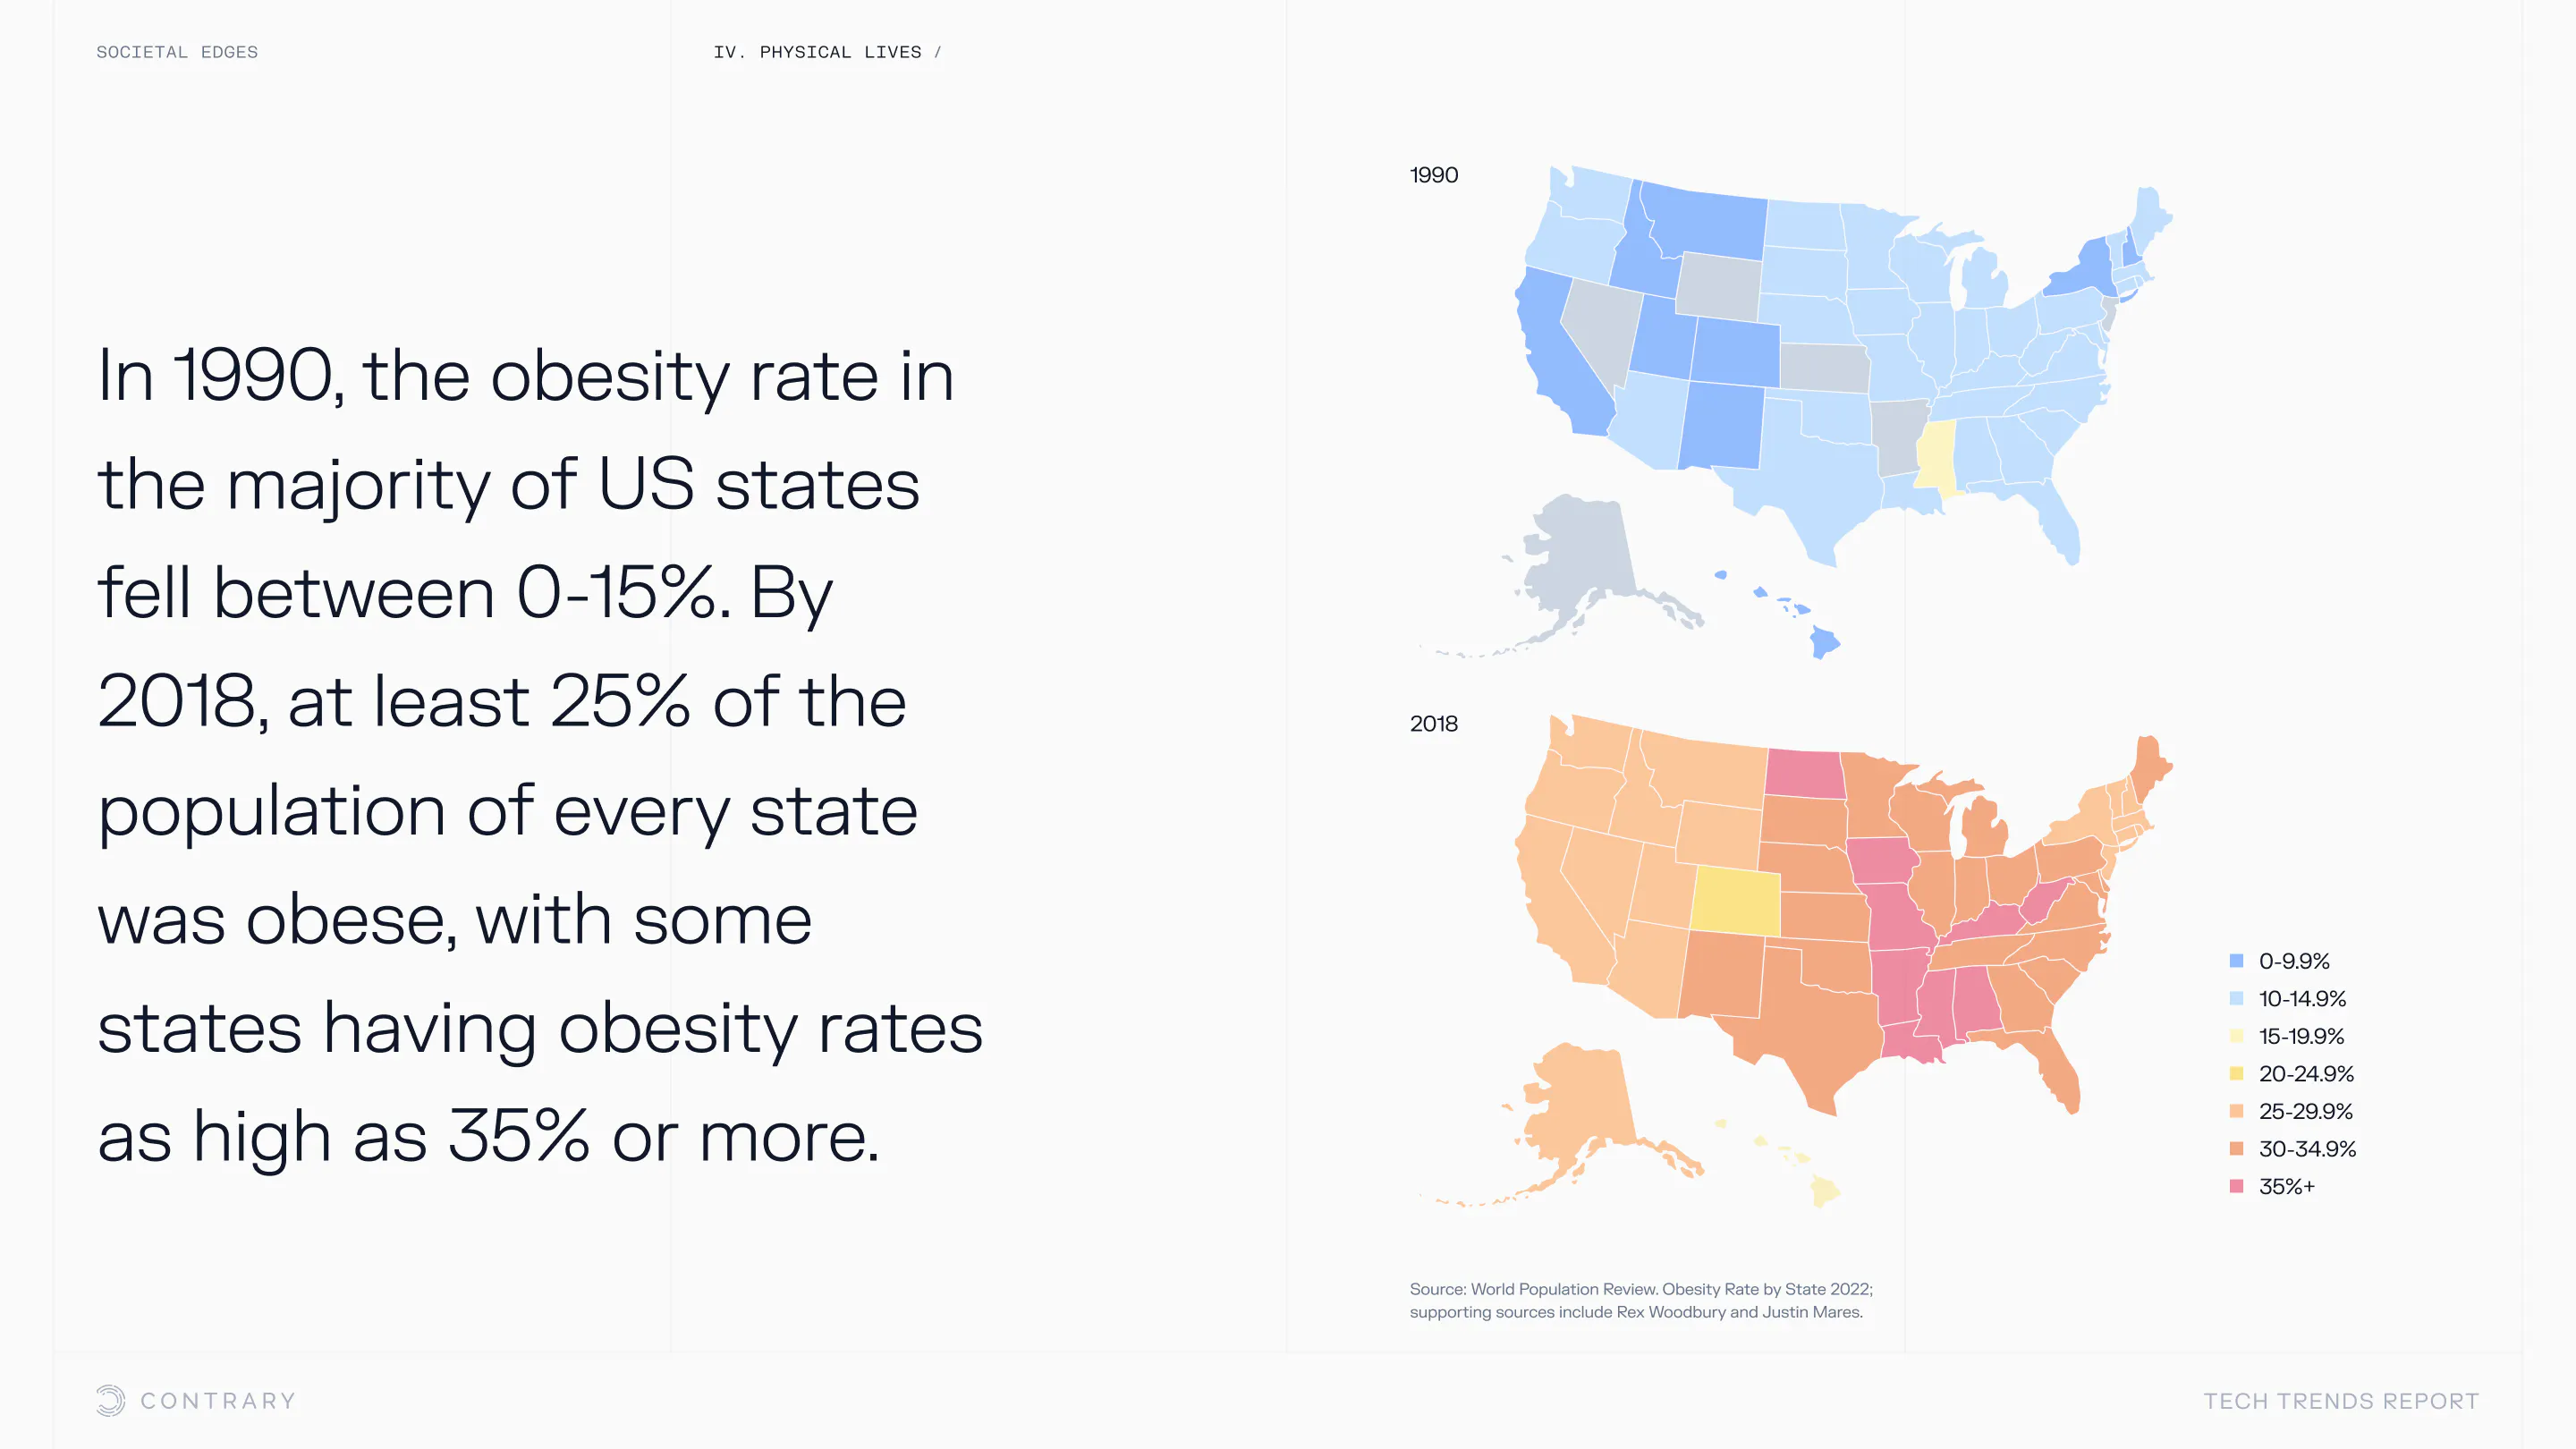

An aging population is bringing up a range of increased concerns, from mental health to disease control. Obesity and gastrointestinal cancers are plaguing younger generations. The cutting edge is tackling a system that has unhealthiness woven into it.